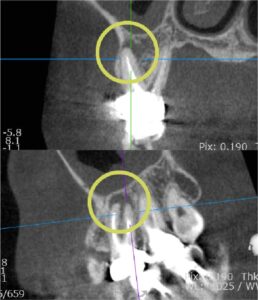

上顎洞炎を伴う根尖病変に対するマイクロスコープ下の根管治療

右上の痛みを訴えて来院されました。 CT撮影の結果、右上6番の根尖に黒い影があり、上顎洞内の粘膜も炎症で厚く腫れていることが確認できました… -